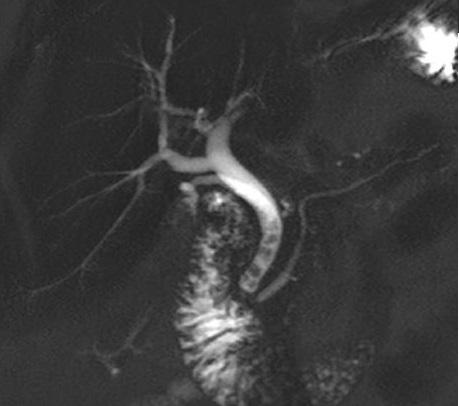

Calcul multiple

situe a la portion inferieure du canal

choledoque . Image radiologique cholangio - IRM des

voies biliaires recontruction en 3D |